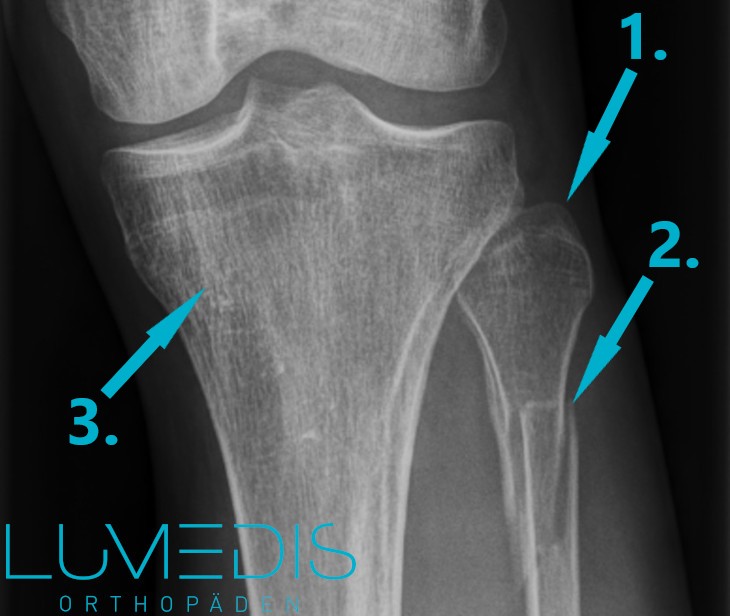

Röntgenbild eines Wadenbeinbruchs mit Kallus

Das Röntgenbild stellt den Goldstandard in der Diagnostik von Knochenfrakturen dar.

Dabei lassen sich Knochenstrukturen im Röntgen besonders detailreich abbilden.

Sobald eine Frakturlinie im Bereich des Wadenbeins erkennbar ist, gilt die Diagnose als gesichert.

Zur besseren Beurteilbarkeit wird das Röntgen des Wadenbeins stets in zwei Ebenen durchgeführt.

Röntgenbild eines Wadenbeinbruchs von vorne